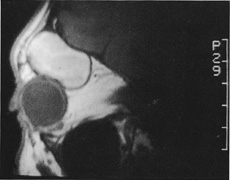

Figure 10. A. Large, well-encapsulated intraconal mass on MR scan. B. Small lateral canthotomy incision will be used to perform lateral orbitotomy and remove the intraconal mass.

Fig. 11. A. Lateral canthotomy incision is made with straight iris scissors. B. Periosteum is elevated off of the lateral orbital rim. C. Wide undermining allows retraction of the skin incision to permit superior and inferior osteotomies to be made with the air-driven saw. D. The bony rim has been outfractured. Because of the distensibility of the skin, it is possible to remove a large bone flap through the small canthotomy incision. E. The intraconal mass is extracted with the aid of the cryoprobe. F. The bone fragment is positioned for resuturing.